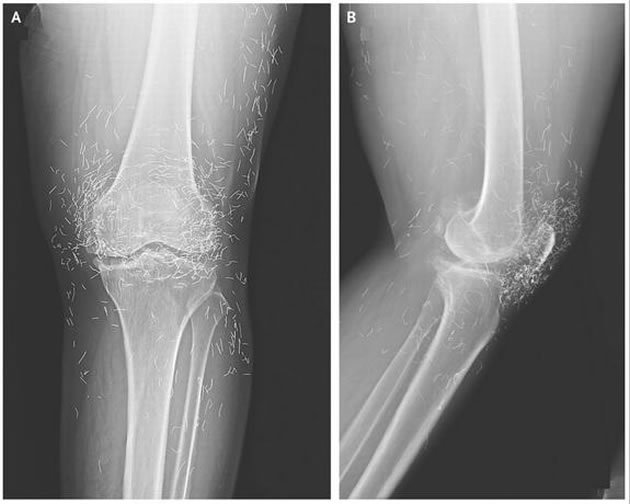

Tudo começou com um problema no joelho, no primeiro momento ela foi diagnosticada com osteoartite, doença degenarativa e que ataca diretamente as articulações.

Os remédios não fizeram efeito, então os médicos pediram um raio-x, ela descobriu que não tinha doença ou lesão alguma, mas sim, pequenos pedaços de ouro presos em sua cartilagem.

Os pequenos pedaços de ouro que estão alojados, devem-se ao tratamento de acupuntura. Em suas sessões, o especialistas deixavam pequenos pedaços da agulha para aumentar a eficácia do tratamento. Como o raio-x indiciou a presença de ouro na cartilagem, é suposto que as agulhas usadas eram feitas deste material.